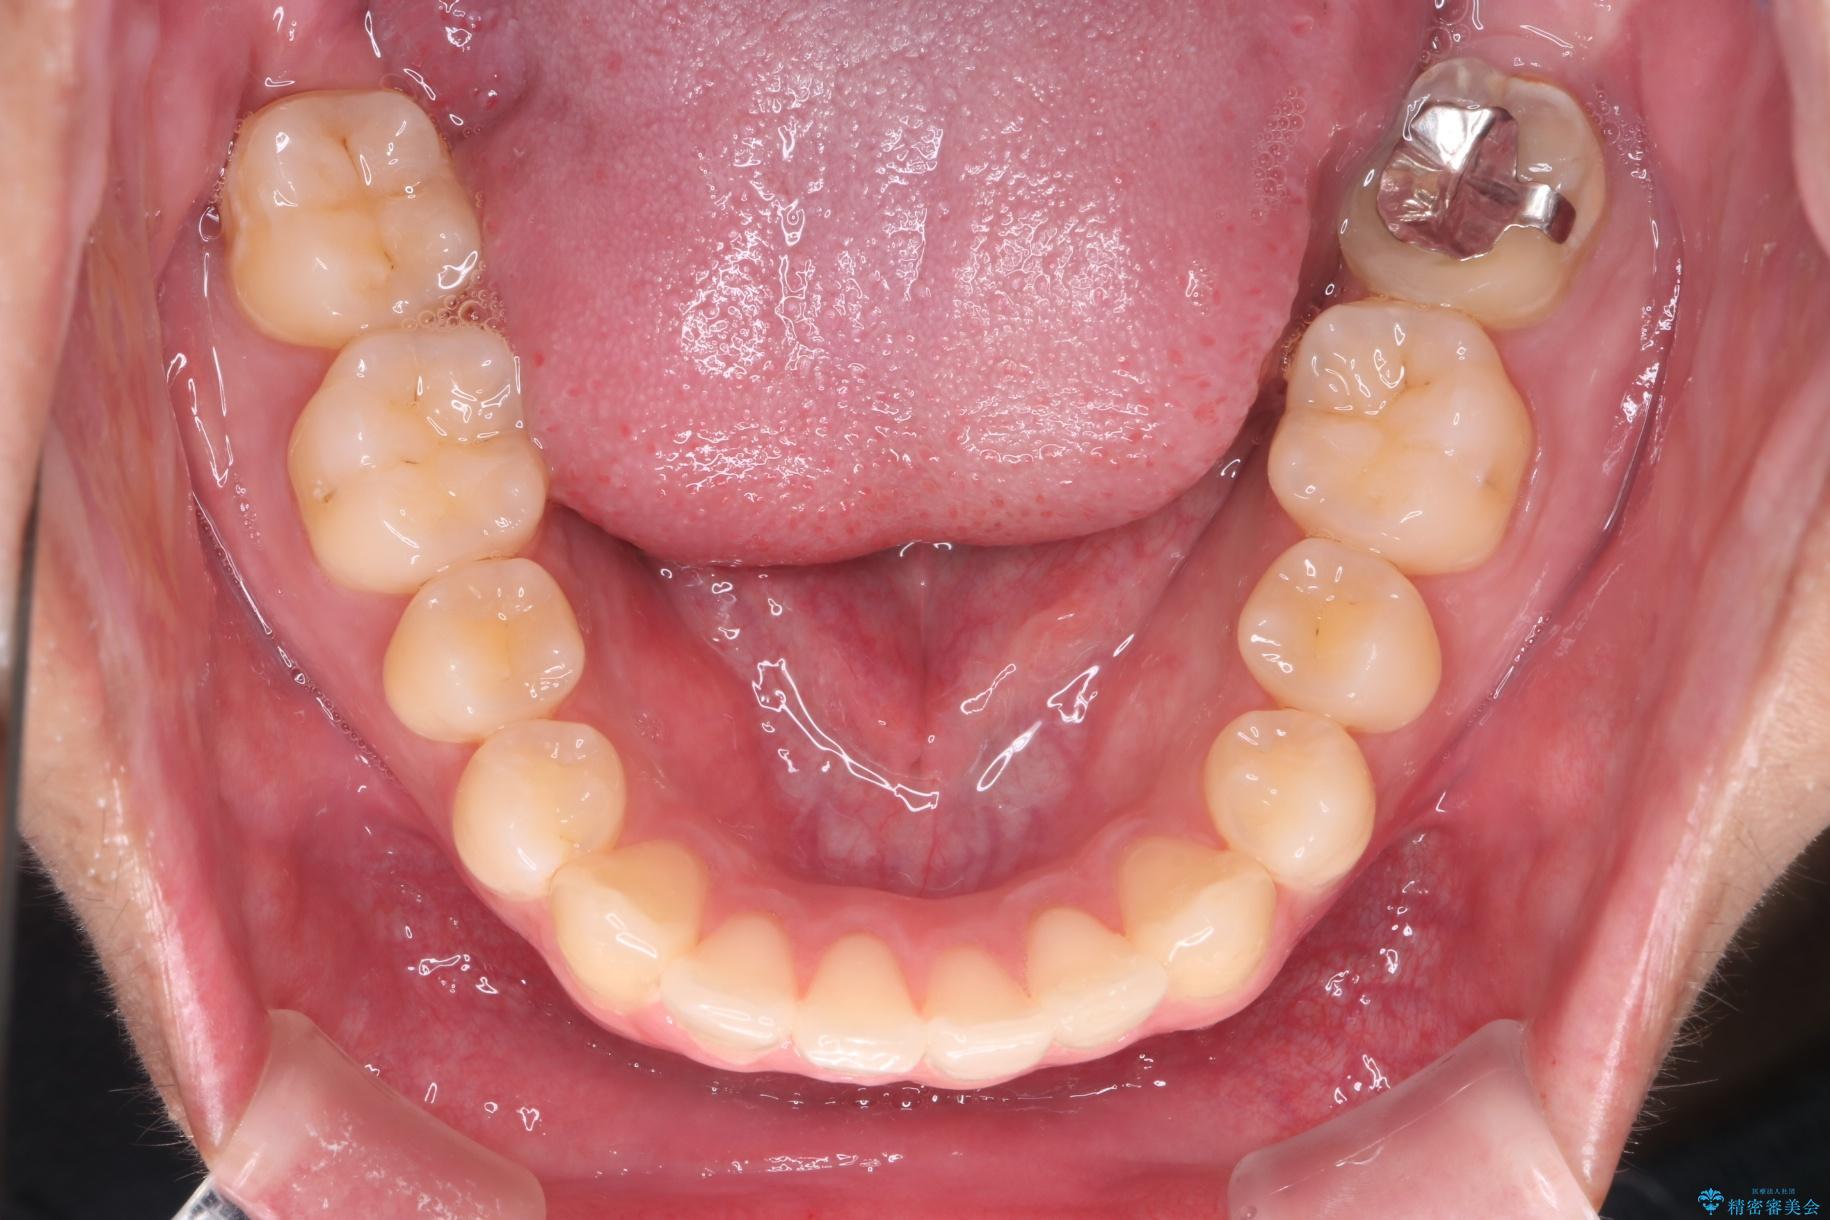

上の八重歯と下の歯のがたつきが気になるとご来院された患者様です。

精密検査の結果、抜歯の必要はないと判断しました。臼歯を遠心移動させ、歯列をワイヤーで整えることでスペースを確保し、IPR(歯と歯の間を削る処置)を加えて歯並びを綺麗にする治療計画を立てました。